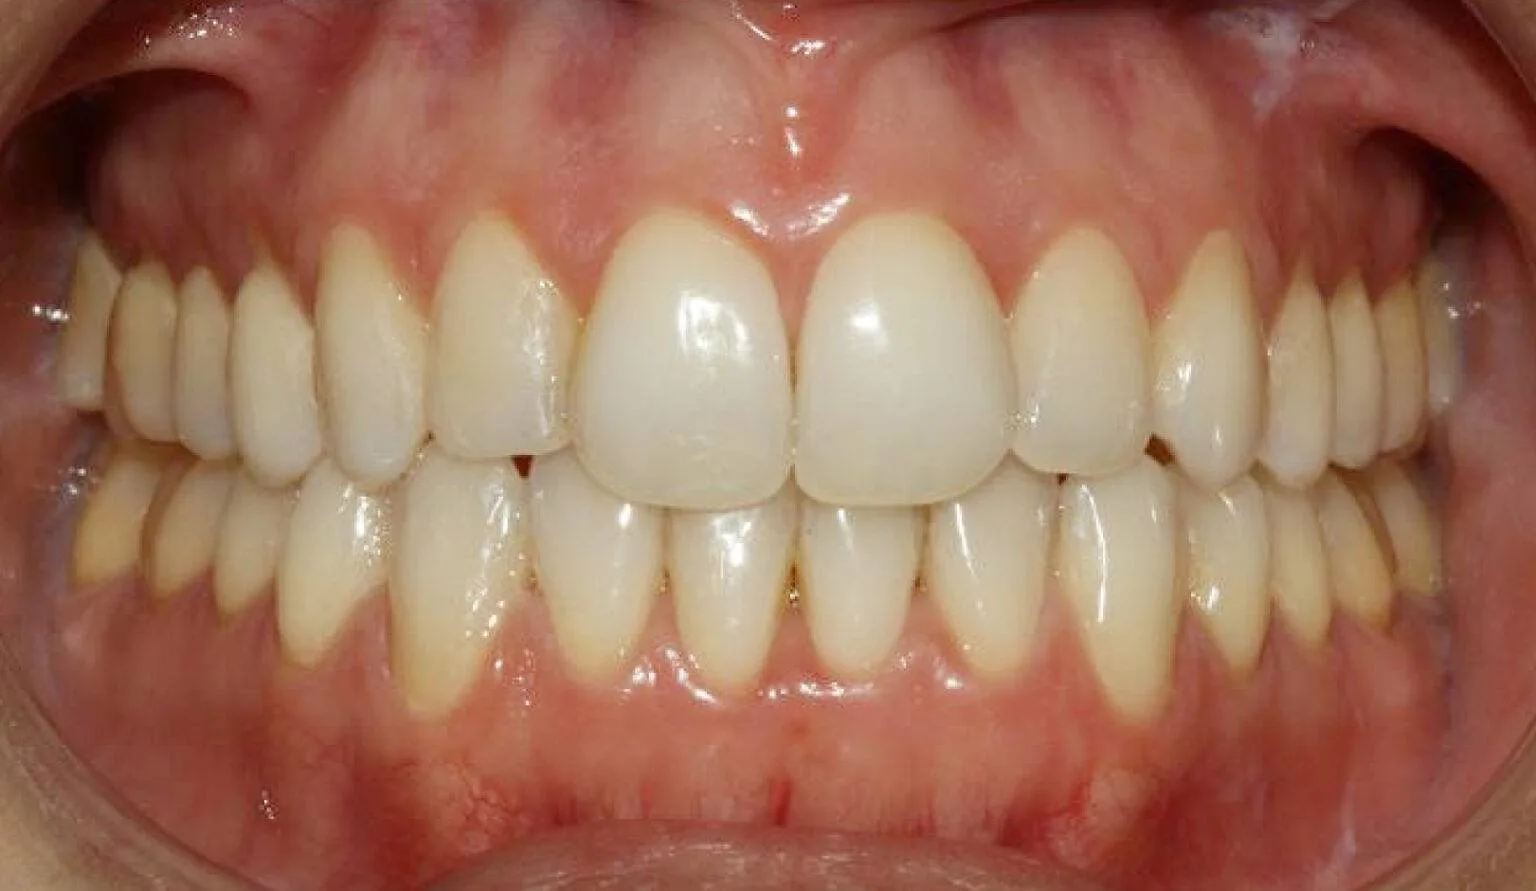

Before overcrowding treatment at SmileBox Clinic After overcrowding treatment at SmileBox Dental Clinic